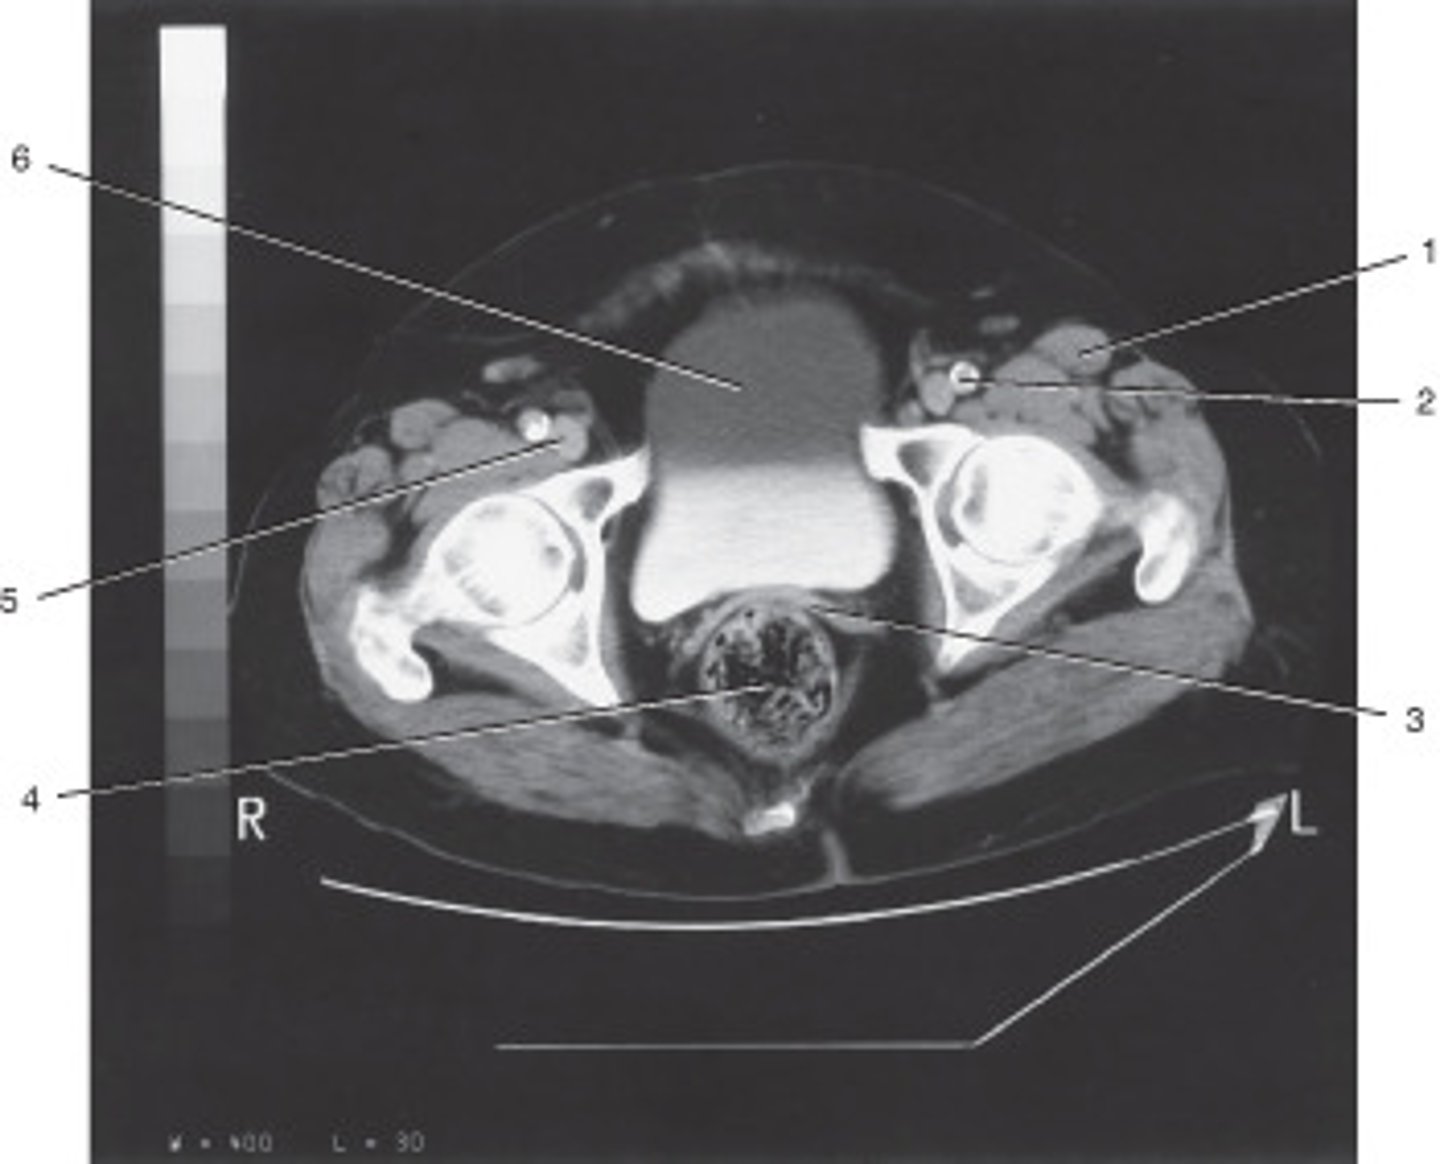

What number corresponds to the acetabulum?

<p>What number corresponds to the acetabulum?</p>

Uterus

Number 4 corresponds to which of the following?

<p>Number 4 corresponds to which of the following?</p>

Ilium

Coccyx

Ovarian Cyst

This ROI has a HU value of +10, given its position in a female bony pelvis, this most likely represents:

<p>This ROI has a HU value of +10, given its position in a female bony pelvis, this most likely represents:</p>

External Iliac Vein

Number 1 corresponds to which of the following?

<p>Number 1 corresponds to which of the following?</p>